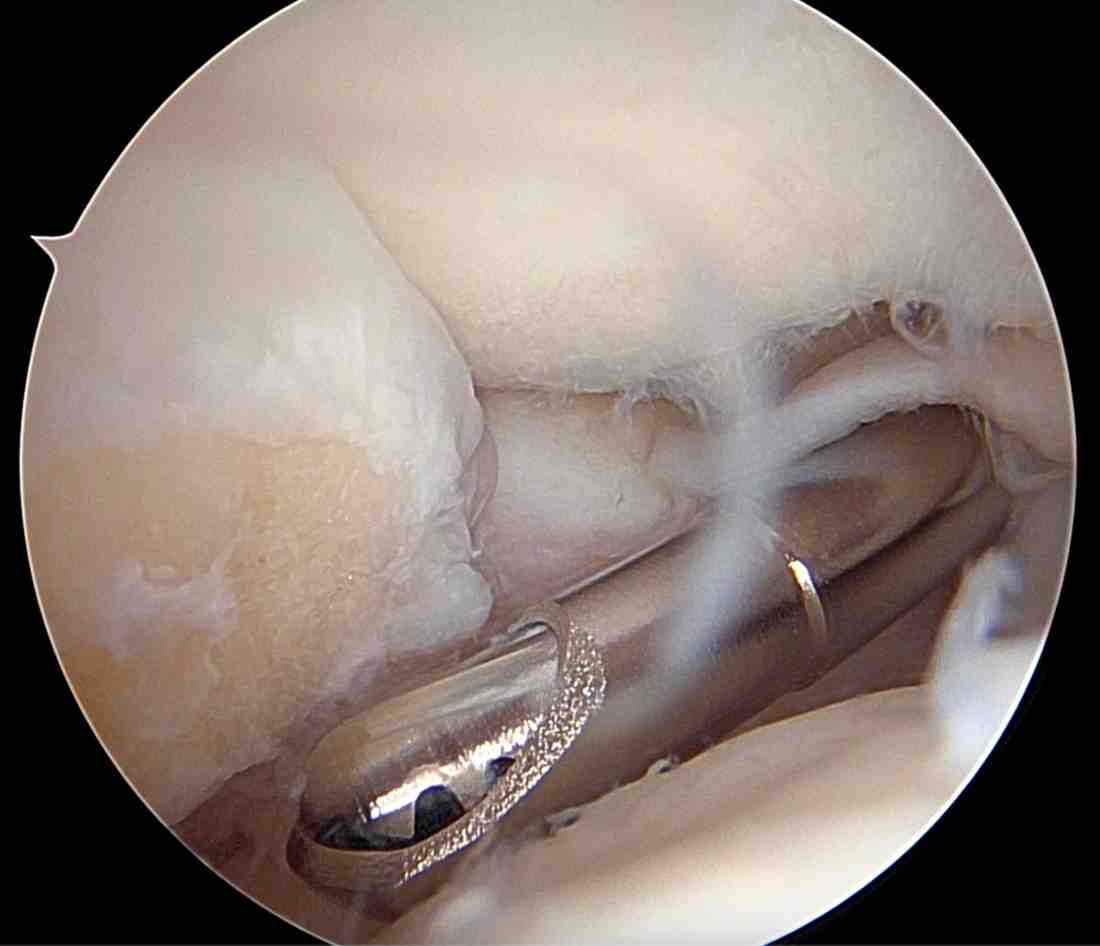

Elbow arthroscopy is performed using an arthroscope—a pencil-thin instrument with a camera and light—inserted into the joint. This allows the surgeon to see the inside of the elbow and guide small surgical tools through additional tiny incisions to perform repairs.

| · Loose bodies (cartilage or bone fragments) – Removal to improve motion and reduce pain | |

| · Osteoarthritis or post-traumatic arthritis – Debridement (removal of bone spurs and damaged tissue) | |